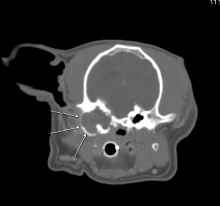

Nasal SCC and Sentinel Lymph Node Identification in Dog

Sentinel Lymph Node Identification in a Dog with Nasal Squamous Cell Carcinoma Fig 1 Cadbury is a 10-year-old Labrador ...